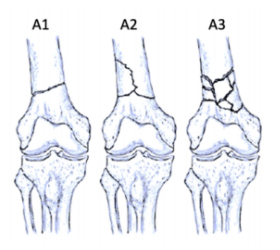

AO/OTA Classification

• Type A: Extra-articular fractures

ao-classification-distal-femur-type-a